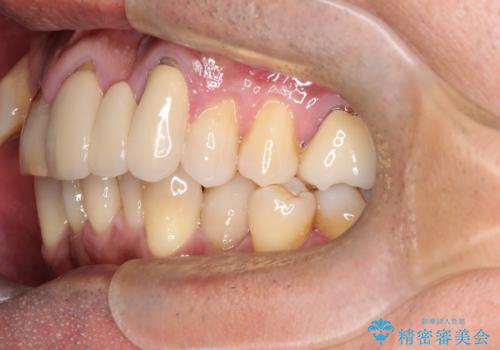

50代からの矯正治療!ブリッジを活かし八重歯を解消

- 50代の患者様で、右上の八重歯と歯並びの乱れを気にされてご来院されました。特に、すでに装着されている前歯のセラミックブリッジを外したくないという強いご希望がありました。精密な検査の結果、八重歯を治すためのスペースが不足しているため、右上の4番目の歯(小臼歯)を抜歯し、そのスペースを利用して歯並び全体を整える治療計画を立案。装置には目立たないインビザラインを採用し、ブリッジを温存しながら八重歯の改善を目指しました。

今回の治療で最も重要だったのは、患者様のご要望通り既存のセラミックブリッジを外さずに矯正を進める点でした。計画通り右上の小臼歯を抜歯し、透明なインビザラインを使用して抜歯スペースを閉じながら、八重歯を正しい位置へ移動させました。ブリッジの形態と調和するに、他の歯の移動を工夫をすることで、複雑な条件をクリア。治療の結果、長年気にされていた八重歯が解消され、見た目が大きく改善しました。50代からでも、ご自身の要望を叶えながら、美しく機能的な歯並びを獲得していただけました。